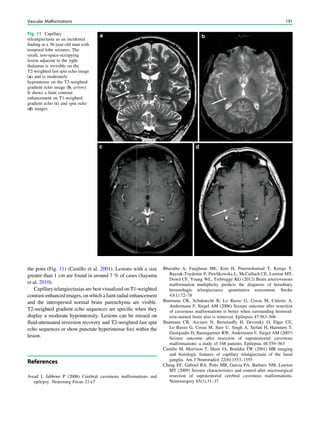

Fig. 1 Digital photogram of the brain surface before placement of a

results of electrical stimulations and ictal/ intraictal EEG activity. Blue

grid contacts represent the eloquent zone, which is the motor cortex in

this case. The black area represents the epileptogenic lesion, defined

as the radiographic lesion that causes the seizures. The yellow area is

the seizure onset zone, defined as the area from which the clinical

seizures are generated. The seizure onset zone is often, but not

necessarily, congruent with the epileptogenic zone, defined as the

cortex area indispensable for the generation of seizures